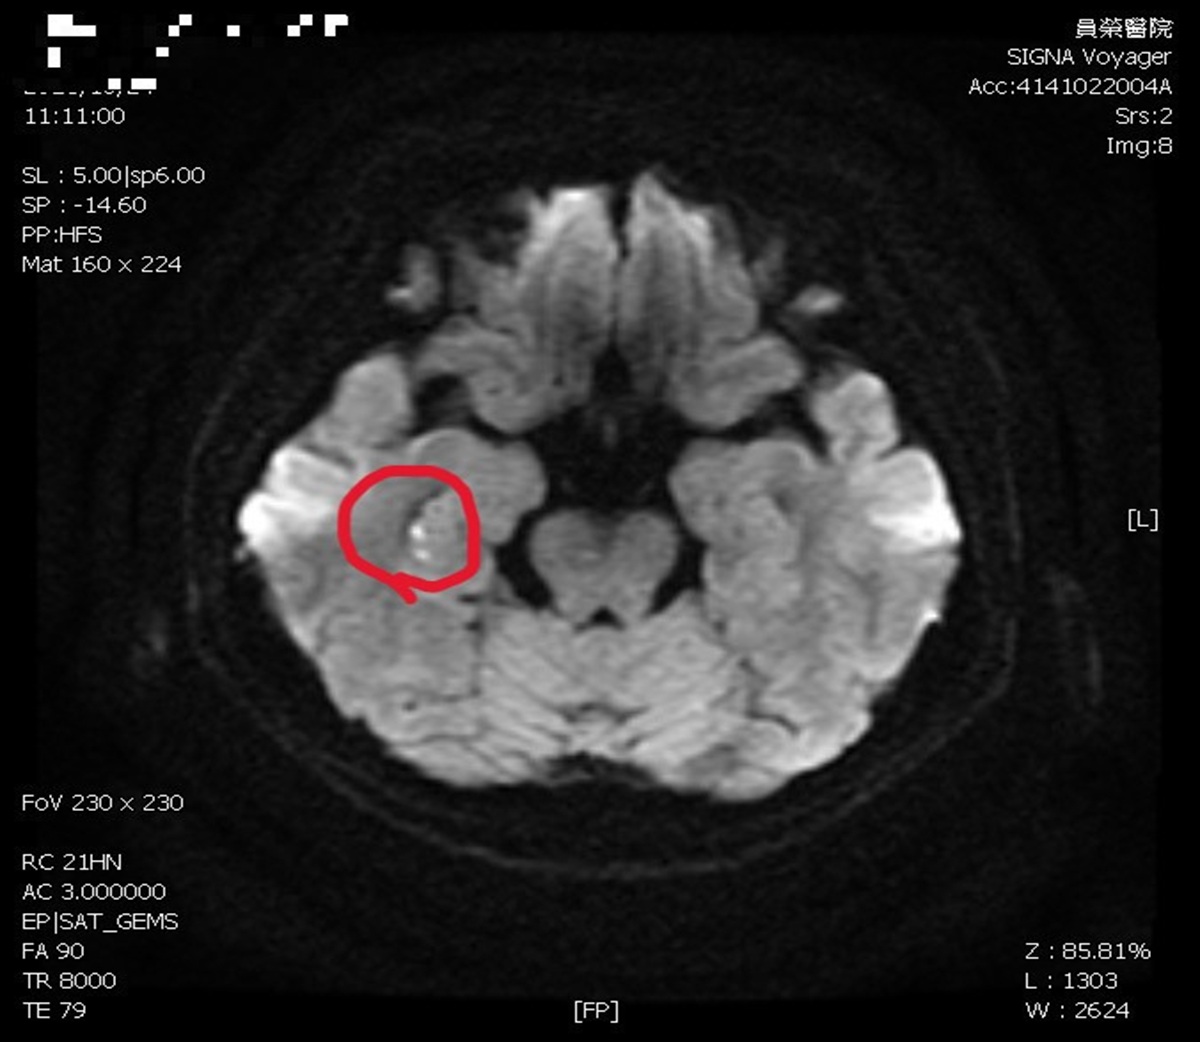

▲陳彥秀醫師表示,患者接受腦波檢查是正常;但核磁共振,看到她右側海馬迴出現一點亮亮的影像。(圖/員榮醫院提供)

陳彥秀醫師表示,患者接受腦波檢查是正常;但核磁共振,看到她右側海馬迴出現一點亮亮的影像。海馬迴與記憶功能密切相關,證實她「短暫性全面失憶」狀況,是因為情緒過於激動,中風所造成。